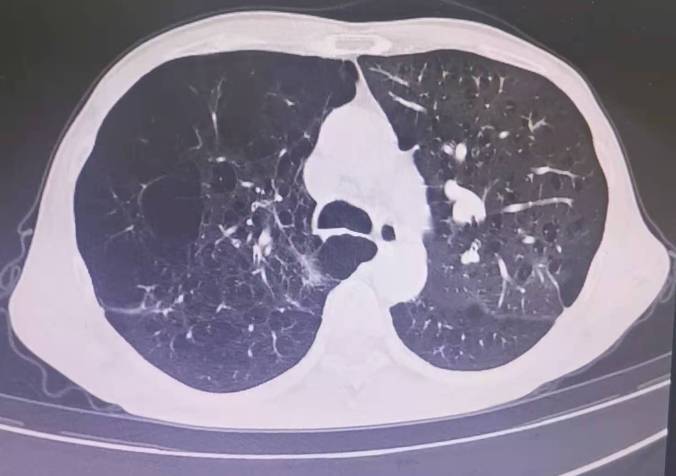

肺气肿CT图片

肺气肿CT图片,肺气肿x线图片

肺气肿的ct表现

两肺肺气肿,胸膜下多发结节 中央小空洞,会是什么病原体?

肺气肿的ct图片

肺气肿的ct表现图片